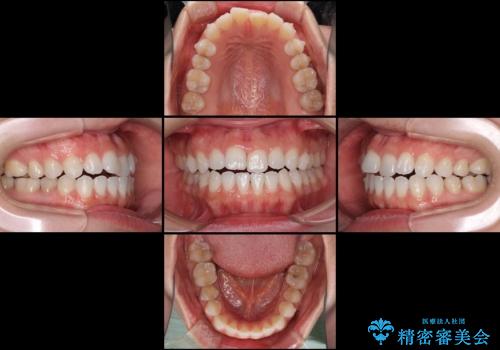

- 上下の前歯の反対咬合を気にして来院された患者様です。

インビザラインを用い、下顎はIPR(歯と歯の間を削る)と歯列全体を後方に移動させ、上顎は前歯を持ち上げることで、反対咬合を改善していくこととしました。

インビザラインによる反対咬合の改善は、上の歯が下の歯を乗り越えていく期間に咬み合わせが非常に不安定となり、治療が長期化することがあります。

こちらの患者様も、一時的に前歯でしか咬めない時期がありましたが、比較的早く咬み合わせが安定し、1年ほどで治療を終えることができました。